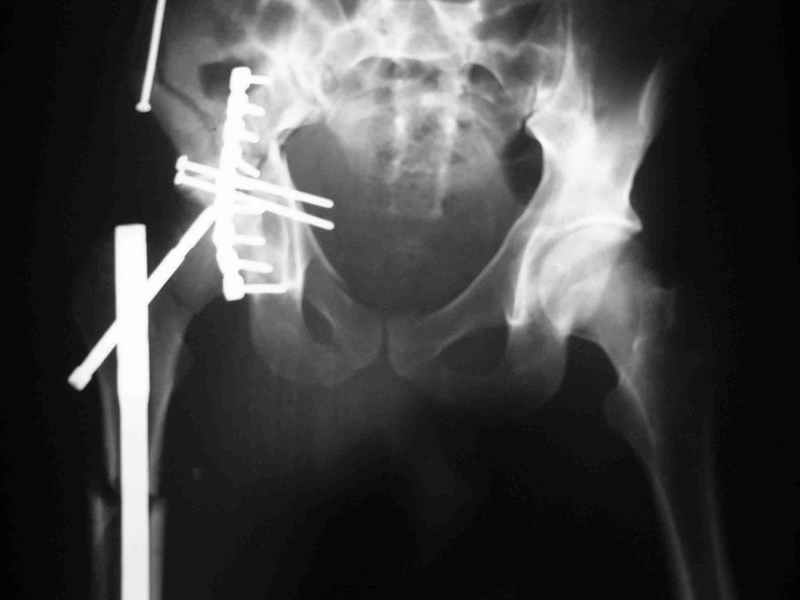

перелом крыла правой подвздошной кости, перелом обеих колонн вертлужной впадины, двусторонний перелом лонных костей (С2.2) повреждение передних связок правого крестцово-подвздошного сочленения,

ипсилатеральный перелом шейки и диафиза бедра.

К сожалению, набора для ретроградного или антеградного реконструктивного штифтования в операционной нет, поэтому доставка заняла н-ное время. Вопрос, который возник у меня- по поводу оптимальной тактики хирургии: вся фиксация в один этап из расширенного доступа или последовательно сначала бедро и позже реконструкция впадины, комбинированный доступ к впадине отдельно к передней и задней колоннам или из расширенного илеофеморального одного доступа. Все-таки решил остановиться на одноэтапном подходе и спустя 5 дней (как раз и наборы привезли) из расширенного илеофеморального доступа сначала фиксировал реконструктивным штифтом Smith&Nephews бедро и

шейку (благо перелом шейки 2 типа -относительно стабильный) затем фрагмент крыла подвздошной кости Lag screw, далее пластина на заднюю колонну и винты в переднюю колонну.(с размерами и направлением винтов ошибка вышла:-((, но интраоперационно у меня была полная уверенность , что винты *ушли* в лонную кость).

Еще раз спасибо за комментарии и готовность помочь с имплантами. Постоп картинки в приложении,